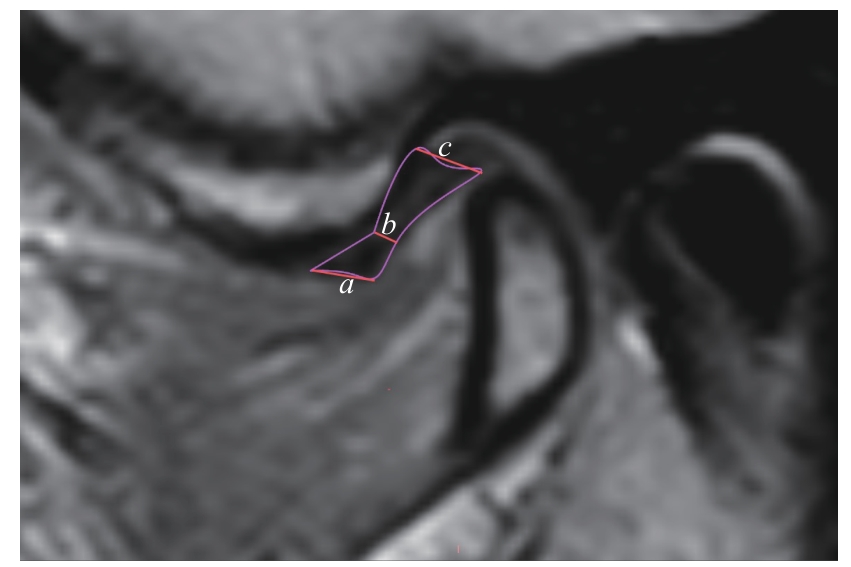

ARAYASANTIPARB R, TSUCHIMOCHI M. Quantification of disc displacement in internal derangement of the temporomandibular joint using magnetic resonance imaging[J]. Odontology, 2010, 98(1): 73-81.

|

| [20] |

YANG Z J, WANG M G, MA Y W, et al. Magnetic resonance imaging (MRI) evaluation for anterior disc displacement of the temporomandibular joint[J]. Med Sci Monit, 2017, 23: 712-718.